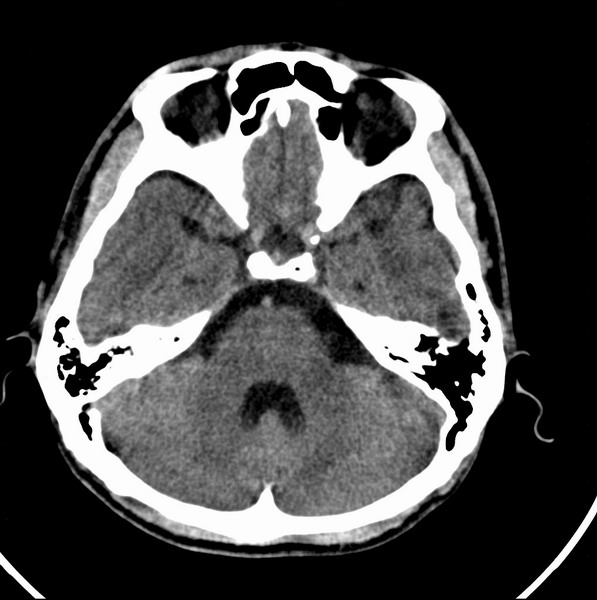

男、29

突发痴呆,失语,记忆减退,反应迟钝二十小时。

左额叶也有类圆形低密度影,同右侧低密度灶近颅底一层同层,病灶周脑实质密度似稍高,成环状,这个没有问题么?